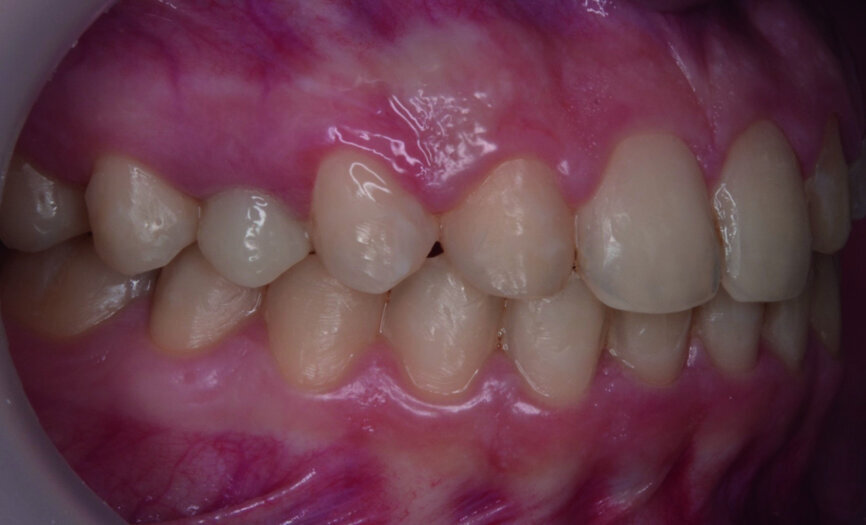

- Gingival height of contour of the upper anterior teeth (Fig. 1): central incisors and canines are more superior than that of the lateral incisors.

Then occlusal analysis (Figs. 11–21) was performed:

- Skeletal Class III (Fig. 17).

- Dental Class I.

- Maxillary hypoplasia with lower arch dental compensations.

- Insuficient overbite and overjet.

- Upper spacing due to the laterals agenesis (Fig. 18).

- Upper midline deviated to the right.